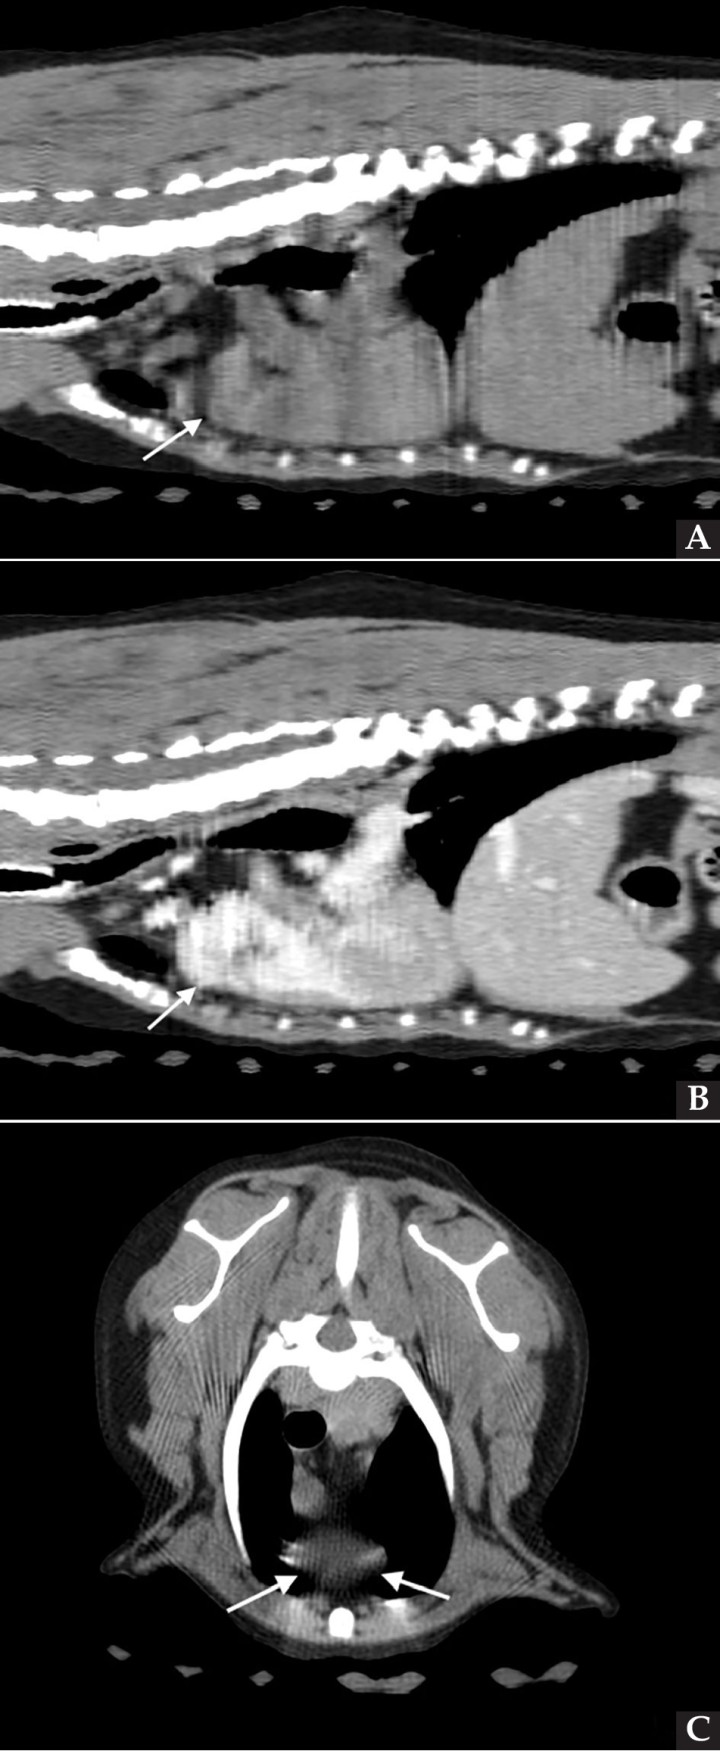

Se realizaron radiografías torácicas y en la proyección lateral derecha se observó, craneal a la silueta cardiaca, una opacidad tejido blando mal definida que producía efecto silueta positivo con esta. La tráquea se visualizó desplazada dorsalmente y el atrio izquierdo aumentado de tamaño. El parénquima pulmonar mostraba un aumento de opacidad en su área caudodorsal, compatible con un patrón pulmonar intersticial no estructurado difuso, el cual se consideró normal debido a que la radiografía fue tomada en fase espiratoria inicial y a la condición corporal del paciente. En la proyección ventrodorsal, el mediastino craneal se observó en el límite superior de tamaño, presentándose un tamaño dos veces superior a la anchura de la vértebra torácica (Fig. 1). Este cambio es compatible con una imagen artefactual secundaria a la leve rotación que presenta la radiografía y a la condición corporal del paciente. El diagnóstico radiológico más probable fue una masa mediastínica craneoventral y cardiomegalia izquierda. En la ecocardiografía transtorácica se confirmó el diagnóstico de enfermedad degenerativa de la válvula mitral (EDVM), presentando engrosamiento, prolapso e insuficiencia valvular, dilatación del atrio izquierdo (AI/AO=1,9) y leve aumento de las dimensiones diastólicas del ventrículo izquierdo normalizado al peso del paciente (NLVDD=1,7). Las presiones de llenado intracardiacas se estimaron como normales, ya que el flujo transmitral presentó un patrón de relajación anómala y la velocidad pico de E fue de 0,8 m/s. En función de estos hallazgos se confirmó el diagnóstico de enfermedad degenerativa valvular mitral con cardiomegalia izquierda y sin hallazgos compatibles con insuficiencia cardiaca congestiva, por lo tanto en estadio ACVIM B2. En las vistas ecocardiográficas paraesternal derecha de 4 cámaras y apical izquierda de 4 cámaras se visualizó una estructura redondeada y anecógena de 15 mm, con flujo sanguíneo en Doppler color, adyacente al corazón (Fig. 2). Este hallazgo es compatible con dilatación aneurismática de las estructuras vasculares o las cavidades cardiacas, si bien no se pudo establecer continuidad con ninguna de ellas en la ecografía. La valoración con Doppler pulsado de los tractos de salida del ventrículo izquierdo y derecho mostró la repetición de un perfil de flujo con disminución del área bajo la curva en el segundo latido con respecto al precedente.

<p>Radiografías torácicas en proyección lateral derecha (<strong>A</strong>) y ventrodorsal (<strong>B</strong>) donde se visualiza el área de opacidad de tejido blando craneal a la silueta cardíaca (flechas blancas). En la proyección ventrodorsal se visualiza el mediastino craneal que se presenta en el límite superior de grosor (flechas rojas).</p>

Figura 1

Radiografías torácicas en proyección lateral derecha (A) y ventrodorsal (B) donde se visualiza el área de opacidad de tejido blando craneal a la silueta cardíaca (flechas blancas). En la proyección ventrodorsal se visualiza el mediastino craneal que se presenta en el límite superior de grosor (flechas rojas).

<p>Imágenes de Tomografía Computarizada. Reconstruidas en plano sagital, simples (<strong>A</strong>) e inmediatamente tras la administración del contraste (<strong>B</strong>), en plano transversal, simples (<strong>C</strong>).</p>

Figura 4

Imágenes de Tomografía Computarizada. Reconstruidas en plano sagital, simples (A) e inmediatamente tras la administración del contraste (B), en plano transversal, simples (C).